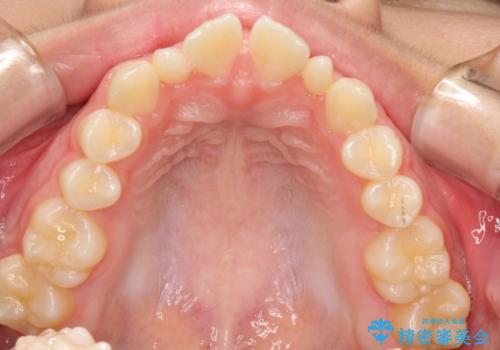

上あごの2番目の歯は矮小歯といって、生まれつき小さい歯となる事がよくあります。

このような場合、矯正によりスペースを集め、本来あるべき形態にセラミックで修正することもできます。

かぶせ物の種類:PFZ standard